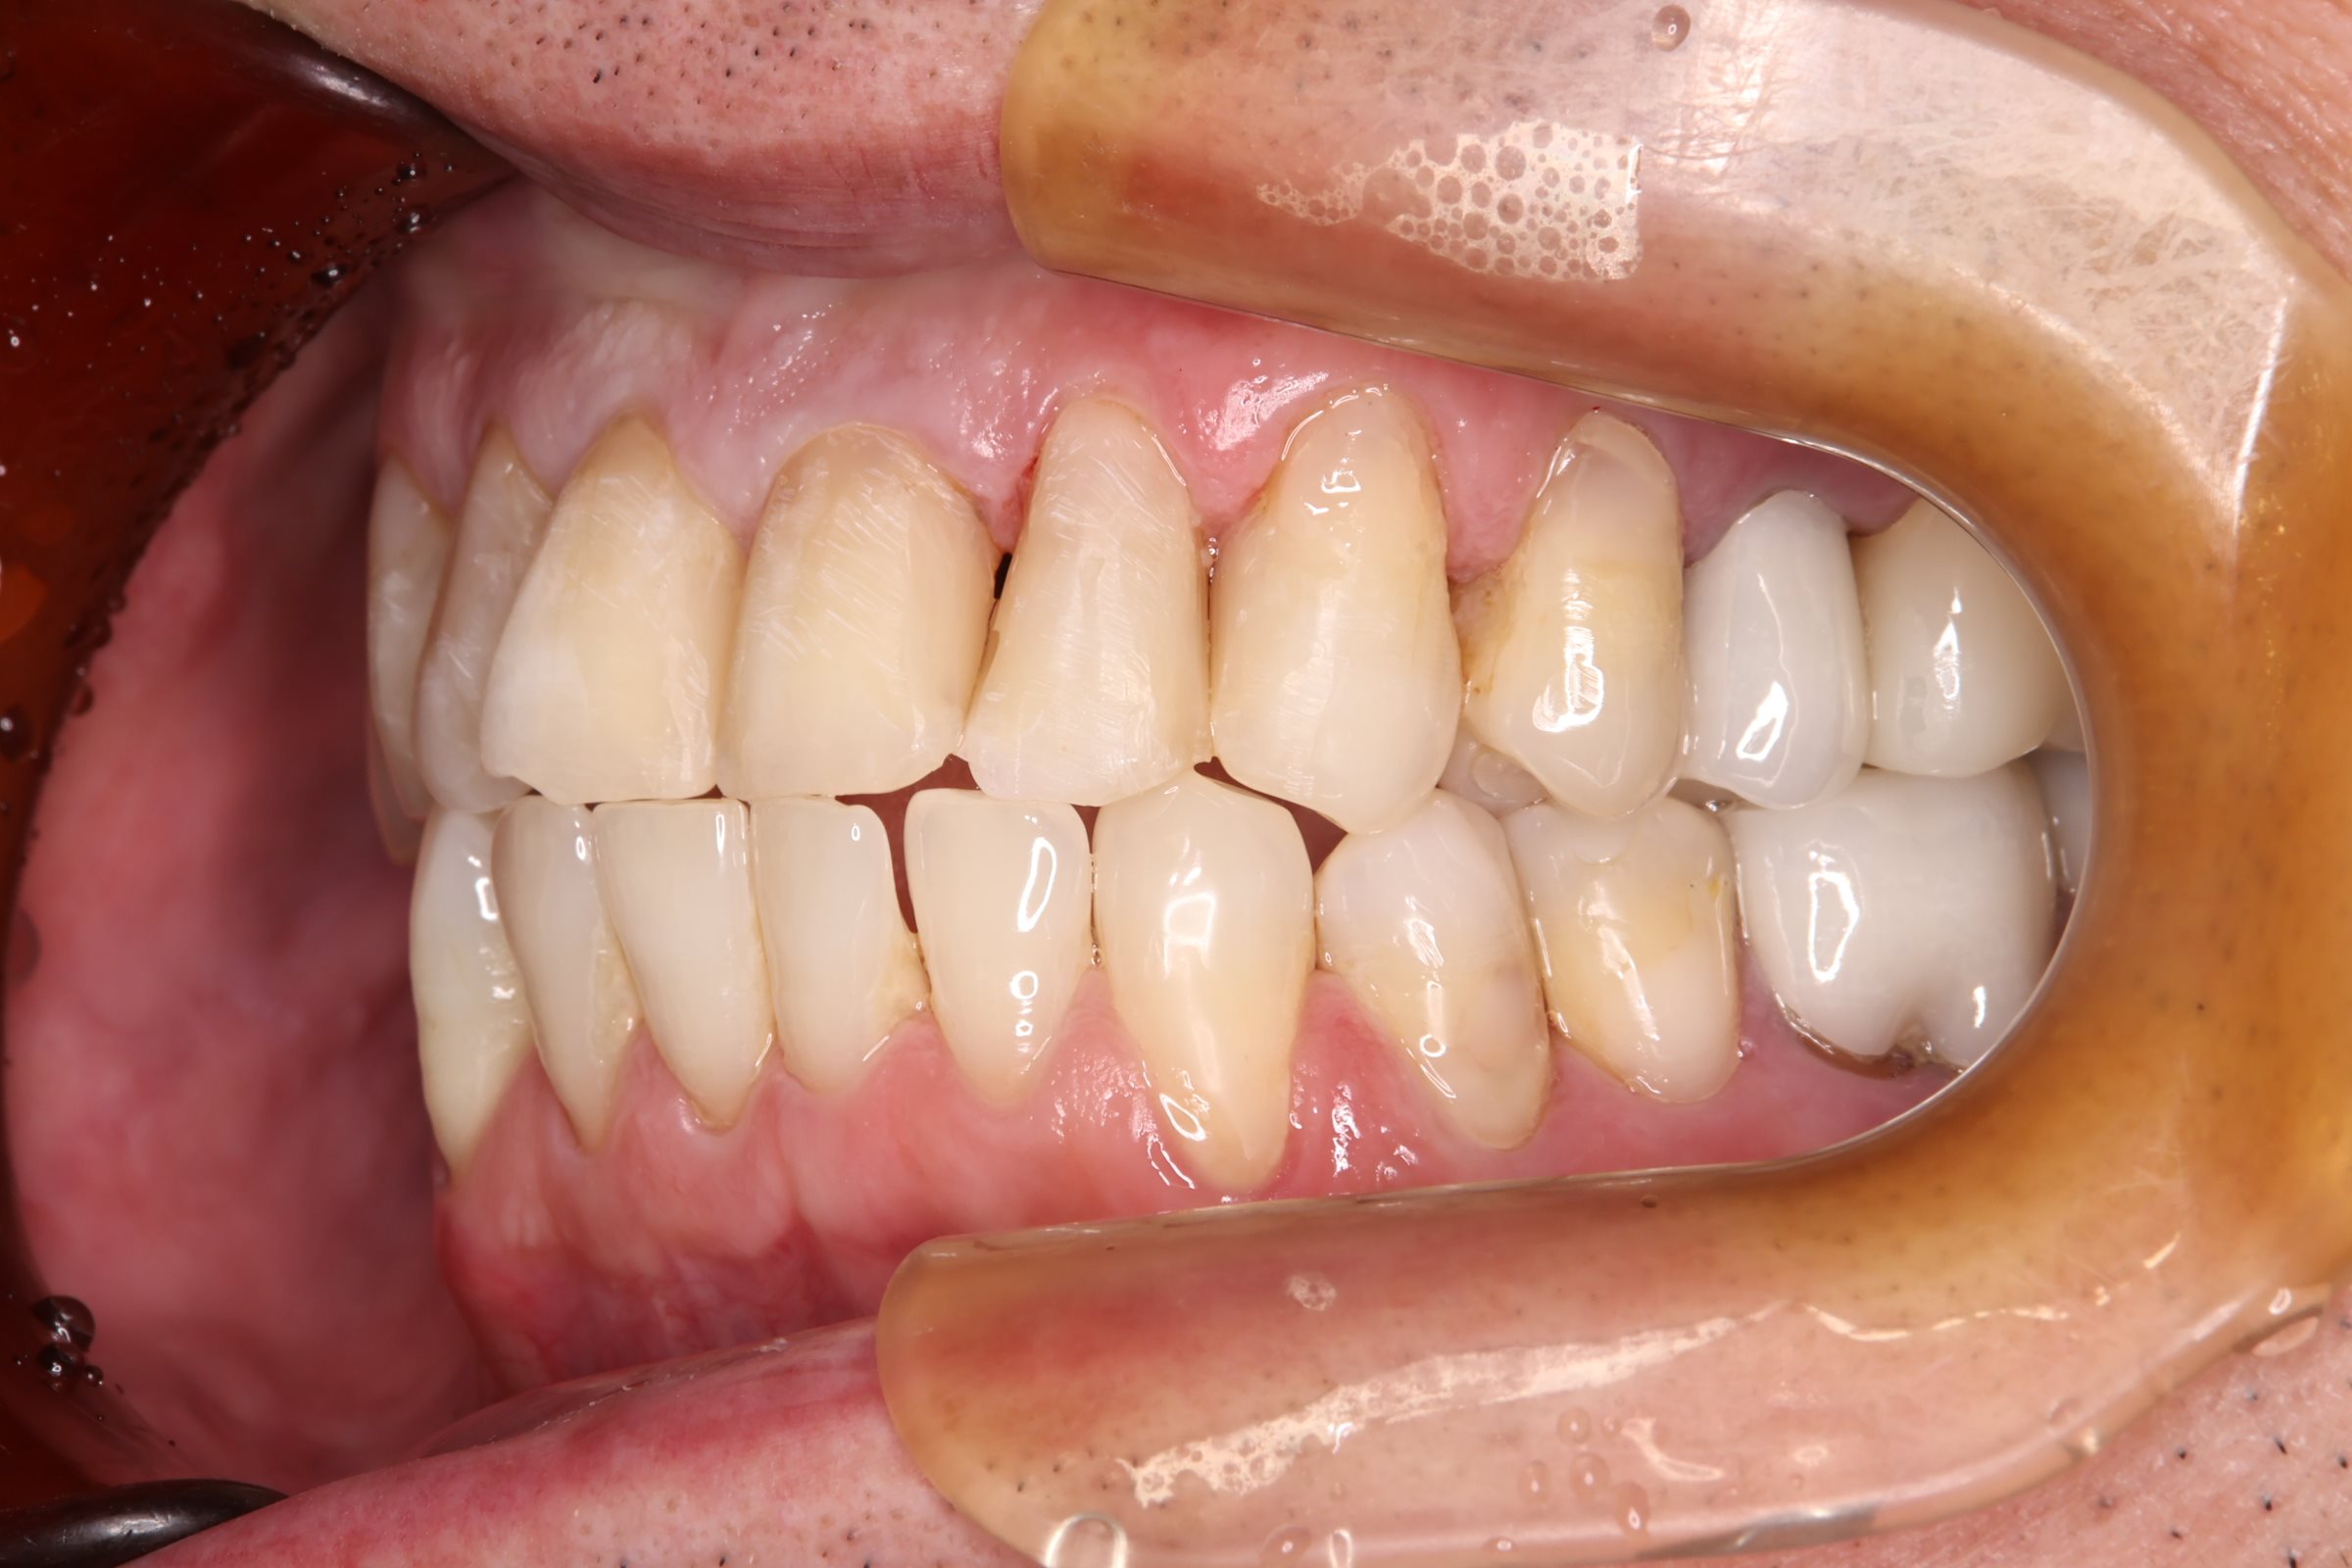

初診時の口腔内の状態:

お口全体に虫歯や歯周病の原因となるプラーク(歯垢)が多く付着していました。右上奥歯は重度の虫歯で歯冠部(歯の頭)が失われており、左下奥歯は過去の治療箇所から細菌が入り込み、根の先に炎症が起きている状態でした。

また、左右の奥歯にはWSD(楔状欠損)があり、知覚過敏も見られました。

単なる虫歯だけでなく、「切端咬合(せったんこうごう)」という噛み合わせの不調和が根本的な問題であると診断しました。この噛み合わせにより奥歯に過度な負担がかかり、知覚過敏や歯の損傷を引き起こしていました。

Before